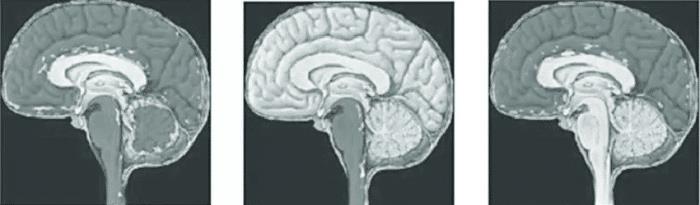

但事情并没有那么简单 。 进入了20世纪 , 医生哈维·库欣等人的病例报告指出 , 患有大脑病变的患者会死于呼吸停止和随后的循环衰竭 。 越来越多的人认为死亡有一个统一的医学概念:所有人类死亡在解剖学上都与大脑有关 。 也就是说 , 人的死亡包括意识的不可逆转的丧失 , 以及呼吸能力的不可逆转的丧失 。

这两种基本能力存在于大脑中 , 代表了人类感知环境并与其相互作用的最基本方式 , 死亡是大脑中这些功能不可逆转的丧失的结果 。 伴随着呼吸机的出现 , 在人类历史上首次实现了使用神经学标准诊断死亡的必要性 , 因为如果不加干预 , 使用呼吸机可以一直维持一个人的呼吸 , 然而对于一个已经丧失意识并且不能恢复的人来说这种呼吸终究不是靠自己呼吸 , 拔掉呼吸机就会死亡 , 这种医学干预下的非正常状态当然不能算还活着 。